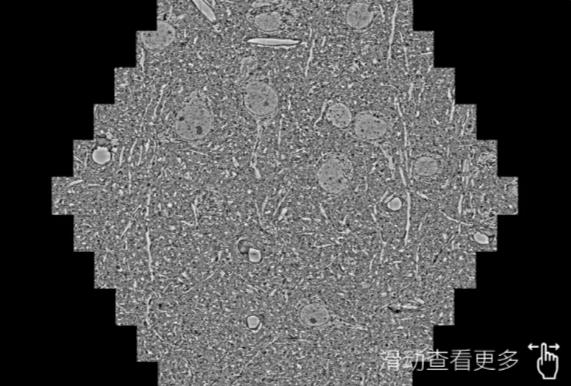

鼠脑切片。左图使用杨浦蔡司杨浦扫描电镜MultiSEM706对165μmx143pm面积区域成像,耗时仅需1.5秒。右图为鼠脑切片中30μm区域放大效果。样品由芝加哥大学B.Kasthuri提供。